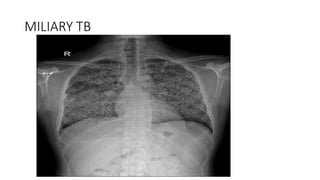

MILIARY TB